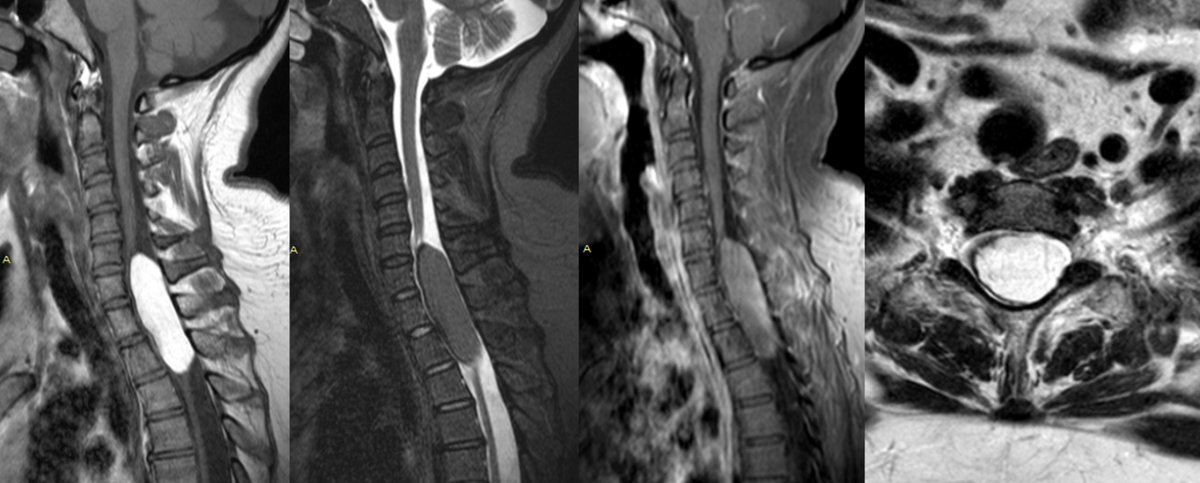

ASSR COTW History: Sensory deficit and neck pain Case c/o Dr. Alex Curry from @PittRadiology #SpineRad #NeuroRad #MedEd #FOAMed #FOAMrad #neuroradiology #radiology

The_ASSR's tweet image. ASSR COTW

History: Sensory deficit and neck pain

Case c/o Dr. Alex Curry from @PittRadiology